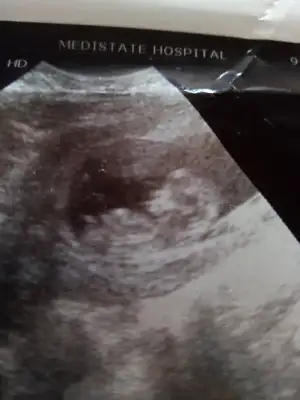

Sanki kız gibi olursa 12 -13 hafta tekrar USG paylasinMerhabalar. Lütfen benim usg lere de bakar misiniz rica etsem?

Ikra meyra 12 hafta oldu doktor söylemedi cinsiyet bir daha gönderim dedim fotomuzu hakkını helal et

12. Hafta ultrasonumuz bize de bakarmisin

Kaç haftalık USG 11 12 13 hafta olmalı sanki kız gibi emin olamadım başka USG de paylasin12. Hafta ultrasonumuz bize de bakarmisin